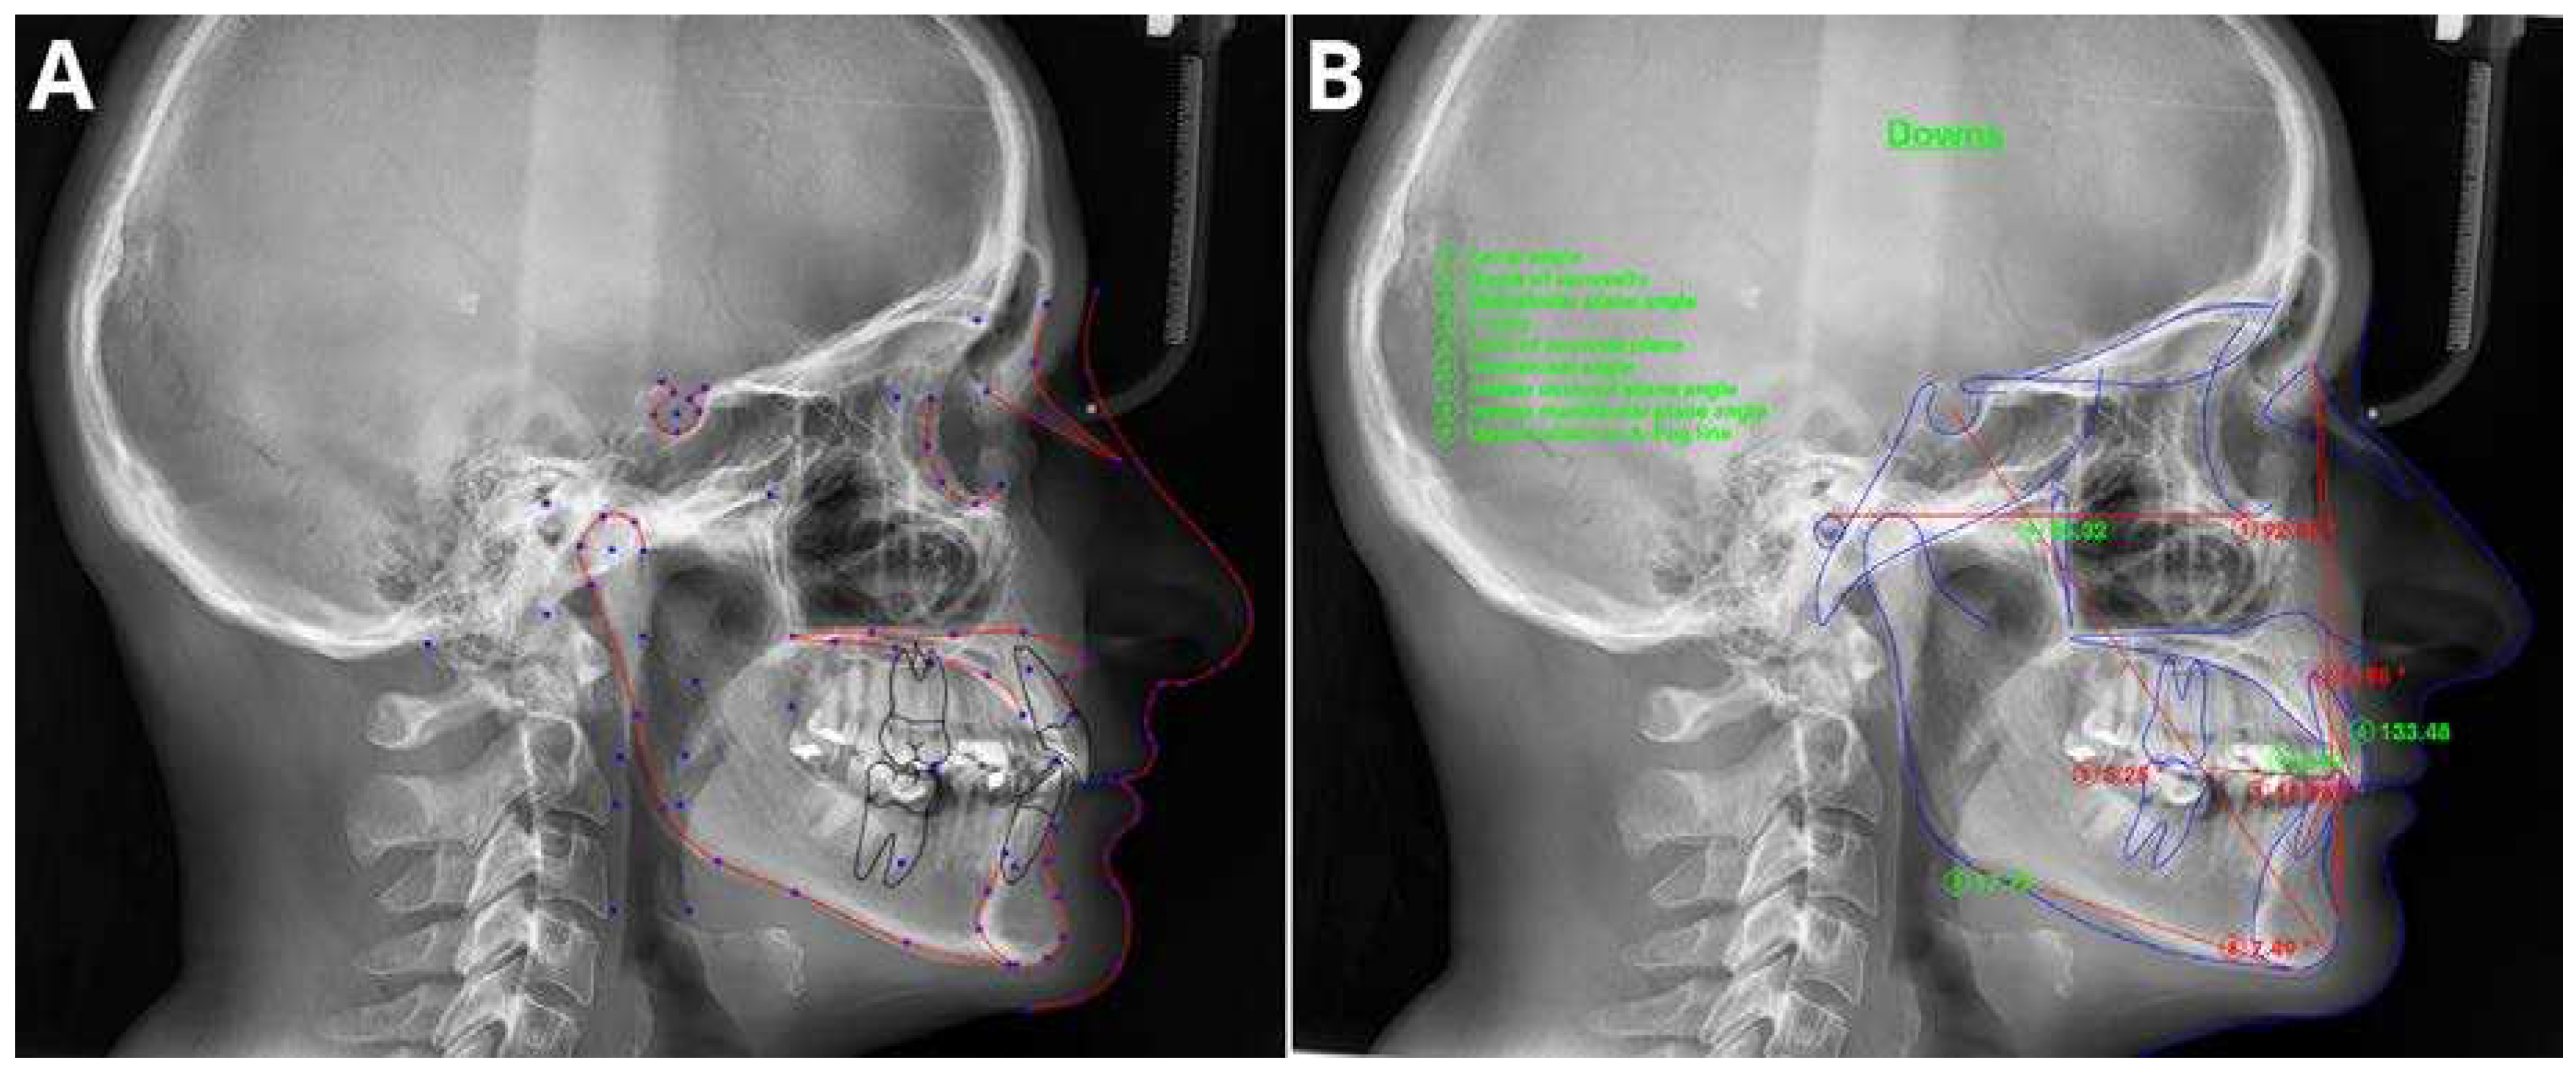

3.2. Cephalometric Analysis

- Leonardi, R.; Giordano, D.; Maiorana, F.; Spampinato, C. Automatic Cephalometric Analysis: A Systematic Review. Angle Orthodontist 2008, 78. [Google Scholar] [CrossRef]

- Chen, Y.J.; Chen, S.K.; Yao, J.C.C.; Chang, H.F. The Effects of Differences in Landmark Identification on the Cephalometric Measurements in Traditional versus Digitized Cephalometry. Angle Orthodontist 2004, 74. [Google Scholar]

- Dias Da Silveira, H.L.; Dias Silveira, H.E. Reproducibility of Cephalometric Measurements Made by Three Radiology Clinics. Angle Orthodontist 2006, 76. [Google Scholar]

- Hwang, H.-W.; Moon, J.-H.; Kim, M.-G.; Donatelli, R.E.; Lee, S.-J. Evaluation of Automated Cephalometric Analysis Based on the Latest Deep Learning Method. Angle Orthod 2021, 91, 329–335. [Google Scholar] [CrossRef] [PubMed]

- Hwang, H.W.; Park, J.H.; Moon, J.H.; Yu, Y.; Kim, H.; Her, S.B.; Srinivasan, G.; Aljanabi, M.N.A.; Donatelli, R.E.; Lee, S.J. Automated Identification of Cephalometric Landmarks: Part 2-Might It Be Better than Human? Angle Orthodontist 2020, 90. [Google Scholar] [CrossRef]

- Chung, E.J.; Yang, B.E.; Park, I.Y.; Yi, S.; On, S.W.; Kim, Y.H.; Kang, S.H.; Byun, S.H. Effectiveness of Cone-Beam Computed Tomography-Generated Cephalograms Using Artificial Intelligence Cephalometric Analysis. Sci Rep 2022, 12. [Google Scholar] [CrossRef] [PubMed]